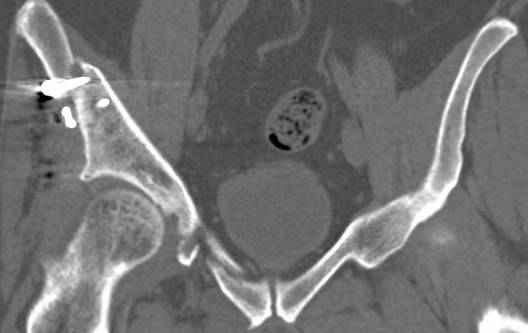

высылаю дополнительно сканы.

итак, второй вариант: высокий двухколонный с вовлечением КПС... Ни одно из основных повреждений не репонировано, кроме задней стенки. Скорее всего попытка реконструкции вертлуги сейчас будет очень травматичной и не очень эфективной, т.е. вероятный риск более значим, чем ожидаемая польза... Лучше подождать, и потом сразу эндопротез

подождать сколько, чего? такая дыра в задней колонне не закроется никогда.

потом эндопротез какой? в такой ситуации приходит на ум Burch-Schneider cage, в 35 лет, дальше что делать?